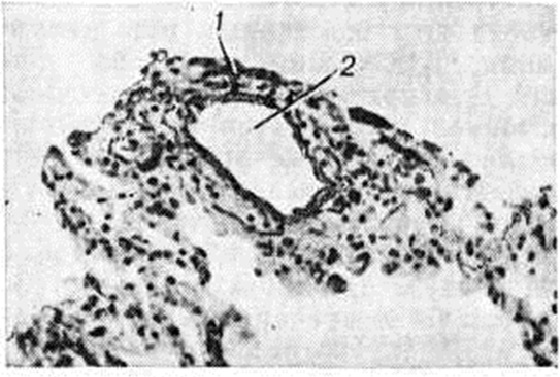

Изменения сосудов лёгких при Гипертензия малого круга кровообращения проявляются гипертрофией и склерозом мышечного слоя и развитием межсосудистых анастомозов замыкающего и гломусного типа. Анастомозы замыкающего типа характерны для всех форм Гипертензия малого круга кровообращения, а анастомозы гломусного типа — для первичной Гипертензия малого круга кровообращения и некоторых врождённых пороков сердца. Степень гипертрофии средней оболочки сосуда определяют с помощью индекса Кернохена (1929): отношением толщины средней оболочки к диаметру просвета сосуда, которое в норме соответствует 1 : 8, а при Гипертензия малого круга кровообращения может достигать 1:3, 1 : 2 и даже 1:1. Более точным критерием оценки степени гипертрофии средней оболочки артерии является метод определения площади поперечного сечения средней оболочки.

Прекапиллярная форма наиболее часто развивается на фоне хронический болезней лёгких, сопровождающихся эмфиземой со склерозом альвеолярных перегородок. Возникающее при этом сопротивление кровотоку в капиллярах приводит к переполнению кровью мелких артерий, вследствие чего просвет их растягивается, циркулярный мышечный слой истончается и вместе с тем за пределами внутренней эластической мембраны формируется более или менее массивный продольный мышечный слой (рисунок 1 и 2). В венозном русле отмечается атрофия мышечных элементов, просвет вен спадается, внутренняя оболочка склерозируется.

При гиперволемии малого круга (дефект межжелудочковой перегородки, открытый аортальный проток и другие), помимо значительной гипертрофии средней оболочки мелких ветвей лёгочных артерий с их миоэластозом и последующим миоэластофиброзом, при высокой степени Гипертензия малого круга кровообращения со стороны внутренней оболочки в артериях отмечается большое количество крупных пикринофильных гломусных клеток с крупным ядром (рисунок 3), способных выделять ацетил холин, холинэстеразу, адреналин, которые воздействуют на периферическое кровообращение. В зарубежных исследованиях эти образования часто неправильно трактуют как артерииты или фиброз интимы.

При посткапиллярной форме нарушение оттока из лёгочных вен приводит к гипертрофии мышечных элементов мелких вен лёгкого с последующим склерозом стенки, что вызывает сужение их просвета (рисунок 4). Это наиболее выражено в нижних долях лёгких. Мелкие ветви артерий терминальных и респираторных бронхиол суживаются вследствие гипертрофии средней оболочки (рисунок 5), иногда склероза внутренней оболочки, что является результатом их рефлекторного спазма. В мелких артериях отмечается миоэластоз с последующим фиброзом средней оболочки; капилляры дольше других отделов сосудистого русла лёгких остаются неизменёнными, лишь в стадии декомпенсации отмечается фиброз их стенки и появление сидерофагов (альвеолярные макрофаги, заполненные гемосидерином).